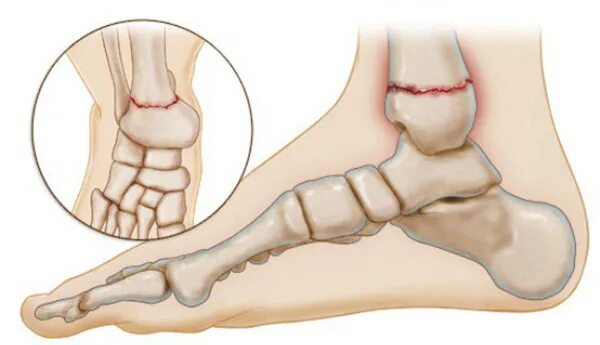

Вывих со смещением